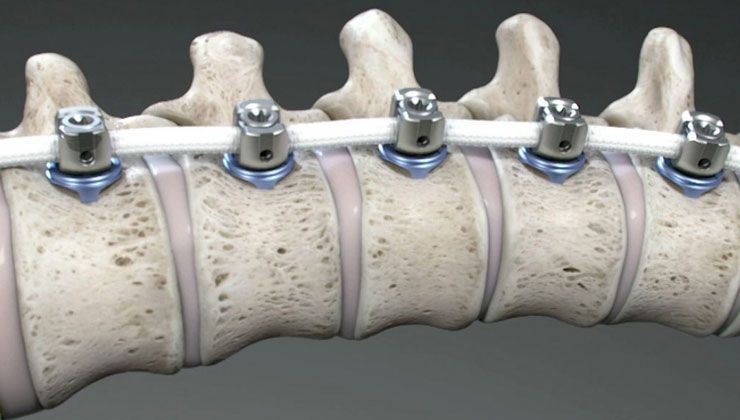

Ailelerin belirtileri görmesi halinde mutlaka en kısa sürede bir ortopedi ve travmatoloji hekimine başvurması gerektiğinin altını çizen Dr. Cengiz, “Ortopedi doktoru detaylı bir muayene yaptıktan sonra omurganın tamamını içeren bir röntgen çekecektir. Burada eğer skolyoz varsa eğrilik hesabı yapılıyor. Omurga eğriliği 10 derecenin altındaysa bunu asimetri olarak tabir ediyoruz. 10 derecenin üzerindeki eğriliklere skolyoz denir ve 10-20 derece arasındaki eğrilikler sadece takip ediliyor. Bunu da yakın takip etmek gerekir çünkü çocuk büyüdükçe eğriliğin derecesi artabilir. 20 dereceden daha büyük eğriliklerde ise korseleme ya da fizyoterapi teknikleri devreye giriyor. 40 derecenin üzerindeki eğriliklerde ise çoğu zaman cerrahi tedavi gerekebiliyor” diye konuştu.